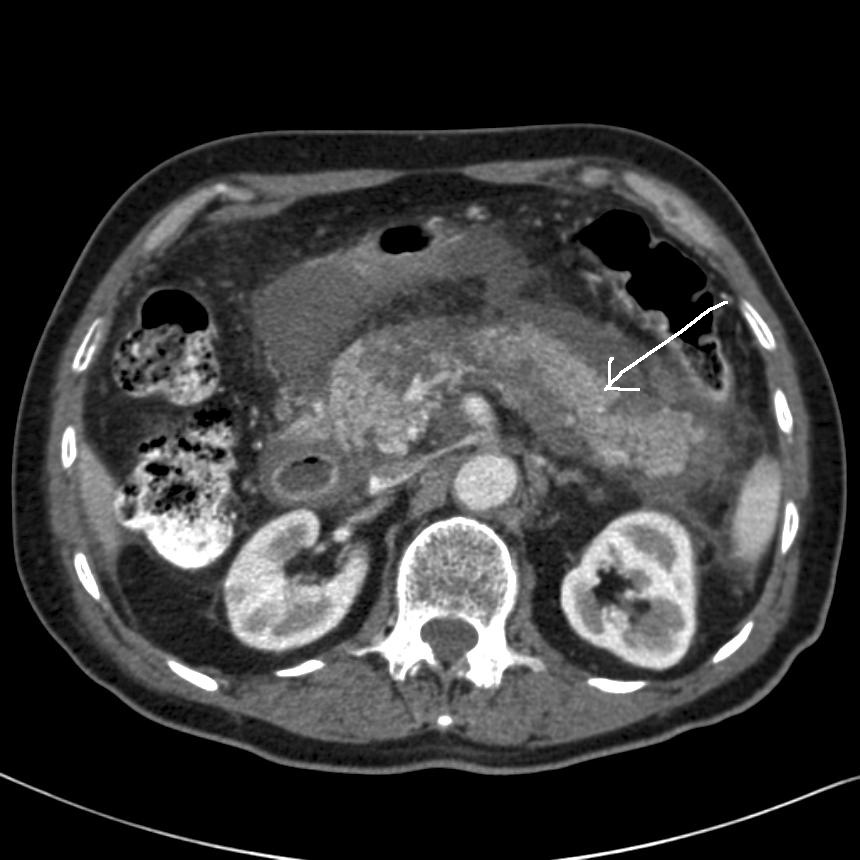

Billedet viser en CT-skanning hos en patient med akut nekrotiserende pankreatitis, hvor der er manglende kontrastudskillelse i store dele af pankreas. (Pilen angiver pankreas placering med nekroser).